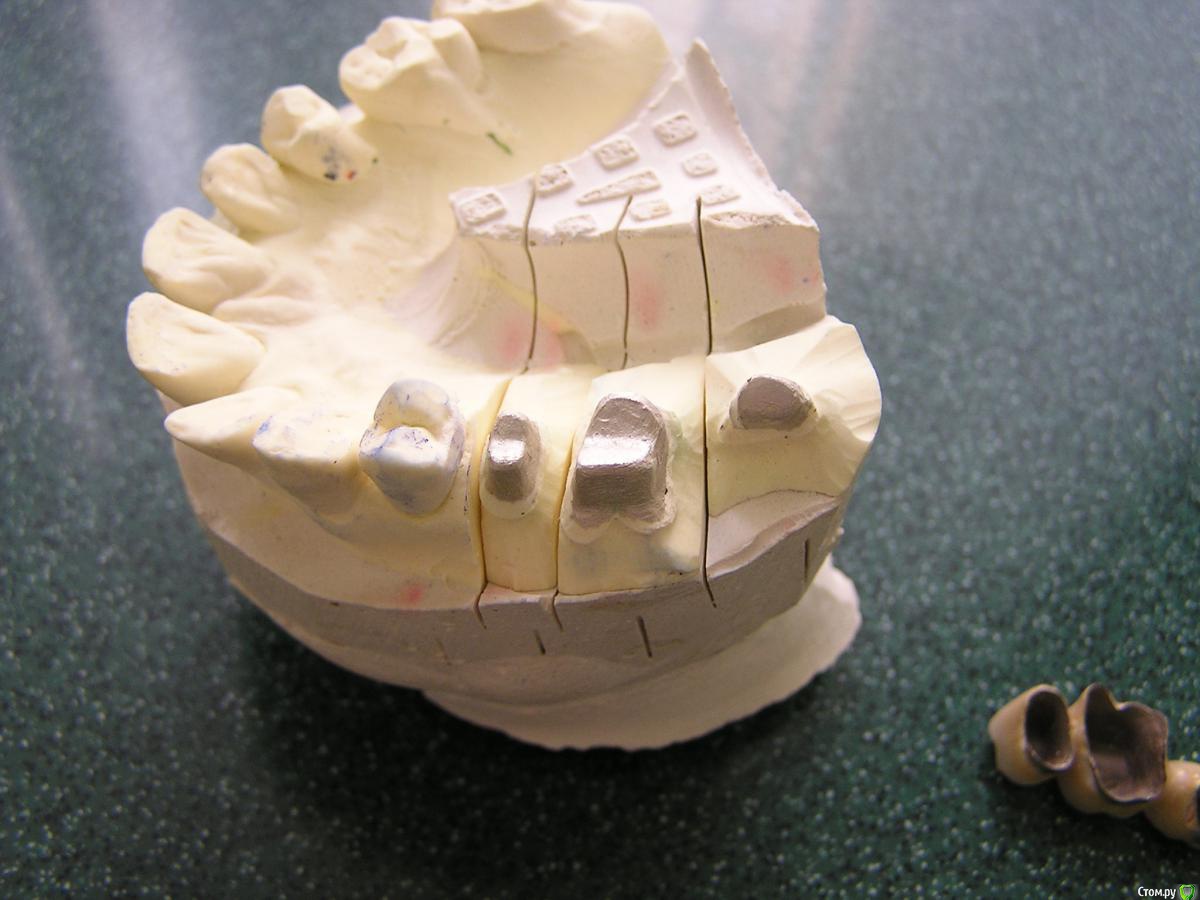

Популярный пост carloss Опубликовано 3 декабря, 2015 Популярный пост Поделиться Опубликовано 3 декабря, 2015 http://savepic.su/6646447.jpg http://savepic.su/6630063.jpg сегодня http://savepic.su/6681262.jpg http://savepic.su/6664878.jpg http://savepic.su/6619823.jpg http://savepic.su/6658734.jpg без чисток и тд.. десять лет вообще не ходила к стоматологу 31 Ссылка на комментарий

carloss Опубликовано 3 декабря, 2015 Автор Поделиться Опубликовано 3 декабря, 2015 (изменено) Можно подробнее, сделали ампутацию? да, раньше часто делал, но обычно срезал один из щечных корней.. большинство стоит до сих пор, правда тут, и шестерка и пятёрка экстремально без феррула, кроме ампутации тока вот, чтобы не обольщались - антагонисты, концевой бюгель)) Изменено 3 декабря, 2015 пользователем carloss Ссылка на комментарий

carloss Опубликовано 4 декабря, 2015 Автор Поделиться Опубликовано 4 декабря, 2015 тоже есть кейс с ампутацией небного корня, пока пациэнт с времянкамиВообще перестал делать ампутации, хотя по старым кейсам щечные корни резал часто даже если в том же сегменте ставил имплантат. Жалко конечно, разленился.. или дань моде..Были случаи и с оставлением только небного корня, что так же экстремально, как тут. Но с ампутацией одного из щечных, до сих пор считаю лучшей альтернативой имплантации, особенно если грядет синус.. Как -то даже диссертацию хотел написать)) - как-чего, особенно важность высокой бифуркации и тд.. надо бы пересмотреть обратно взгляды и включить обратно в прайс услугу. 4 Ссылка на комментарий

carloss Опубликовано 6 декабря, 2015 Автор Поделиться Опубликовано 6 декабря, 2015 одиночки только если отсутствует один из щечных корней.. без небного я бы не рискнул , хотя смотря какие корни останутся, и не всегда оно возможно кстати Ссылка на комментарий